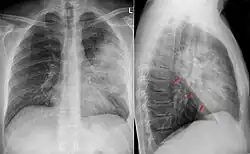

Röntgen

Beim Verdacht auf eine Pneumonie werden in der Regel zwei Röntgenbilder der Lunge angefertigt. Im Röntgenbild stellen sich schlecht belüftete Areale hell dar. Diese können z. B. auf eine Lungenentzündung hindeuten. Diese Veränderung (Infiltrat) entsteht durch die Einwanderung von Leukozyten (Infiltration) und die entzündlich bedingte Schwellung. Sind die luftleitenden Teile der Lunge und die Lungenbläschen nicht betroffen – wie bei einer interstitiellen Pneumonie (Entzündung des Bindegewebes zwischen den Lungenbläschen) –, stellen sie sich im Röntgenbild dar (positives Bronchopneumogramm). Sind hingegen die Lungenbläschen in dem entzündeten Bereich nicht mehr zu sehen, deutet dies darauf hin, dass sich dort Flüssigkeit befindet und die Entzündung in den Lungenbläschen stattfindet wie z. B. bei einer Lobärpneumonie.

Traditionell wird zwischen der typischen, durch Bakterien wie Pneumokokken oder Staphylokokken ausgelösten, und der atypischen, durch Viren, Pilze oder obligat intrazelluläre Bakterien ausgelösten Pneumonie unterschieden. Diese Unterscheidung wird mit einer jeweils charakteristischen Verteilung der Befunde im Röntgenbild assoziiert:

- Die typische Lobärpneumonie beginnt akut (Pneumonia acuta, genannt auch akute Pneumonie[13]), ist auf einen oder mehrere Lungenlappen beschränkt, geht mit Fieber, Schüttelfrost, Husten, eitriger Schleimbildung, reduziertem Allgemeinzustand und typischen Auskultationszeichen einher. Im Blut finden sich Entzündungszeichen: Erhöhte Blutsenkungsgeschwindigkeit, Leukozytose, erhöhte Akute-Phase-Proteine. Pleuraergüsse sind häufig und ausgeprägt. Erreger sind meistens Pneumokokken (Streptococcus pneumoniae), welche als Krankheitserreger der kruppösen Pneumonie[14] erstmals um 1885 von Albert Fraenkel nachgewiesen wurden, aber auch Staphylokokken sowie Klebsiellen, Pseudomonas oder Proteus. Bei älteren Patienten können die Entzündungszeichen (Fieber, typische Blutwerte) bei einer Lobärpneumonie fehlen. Die typischen Phasen der Lobärpneumonie, die einen Zusammenhang zwischen histologischen Strukturänderungen und Pathophysiologie herstellen, sind: Anschoppung > Rote Hepatisation > Graue Hepatisation > Gelbe Hepatisation > Lyse.